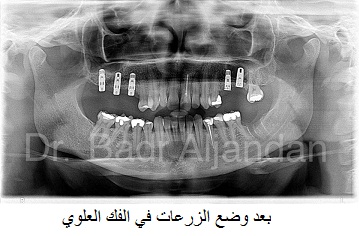

غرسات الأسنان مصنوعة من مادة التيتانيوم. توضع داخل عظام الفك في نفس مكان الأسنان المفقودة. الجزء المعدني الموجود داخل عظام الفك يعمل كوتد بديلا لجذر الأسنان. يتم تركيب الجزء المعدني بواسطة عملية جراحية داخل الفك. وبعد فترة يتم ترابط عظام الفك مع الجزء التيتانيوم مسببا تثبيت قوي للجزء الصناعي داخل الفك. الجزء الأوسط يثبت وتد قوي للأسنان الصناعية.

عند فقدان لسن واحد من المعتاد أن يستعمل تعويض فردي. كل سن صناعي يرتبط بالغرسة الخاصة بها. ممكن استعمال كباري ثابتة و دعامات تستبدل سنتان أو اكثر وتحتاج فقط لعدد 2 أو 3 غرسات (طقم اسنان جزئ). استعمال طقم أسنان كامل (كوبري ثابت) يستبدل كل الأسنان في الفك العلوي أو الفك السفلي. عدد الغرسات تتراوح معتمدة على نوع الاستعاضة الكاملة (متحرك،ثابت). ممكن استعمال طقم متحرك (فوق الطقم) يستند على دعامات في الفك مثل العمود أو الكرة والتجويف ولكن الاستعاضة الثابتة يتم تثبيتها ورفعها بمعرفة الطبيب (طبيب الأسنان).

جراحي الوجه والفكين في عيادتهم يشكلون فريق عمل لزراعة الأسنان في المستشفى محافظين على التعقيم ومكافحة العدوى. يتم اجراء غرسات الاسنان لمرضى المنومين في المستشفى الذين يعانون من بعض المشاكل الصحية أو مشاكل التخدير أو كذلك الذين يحتاجون لاعادة وضع عظام من الفك أو الحوض أو الشظية.

مراحل تركيب الغرسات (الزرعات) من الأوتاد إلى الأسنان الصناعية